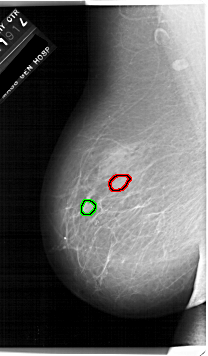

A_1920_1.LEFT_MLO

LEFT_MLO LINES 6751 PIXELS_PER_LINE 3946 BITS_PER_PIXEL 12 RESOLUTION 43.5 OVERLAY

FILE: A_1920_1.LEFT_MLO.OVERLAY

TOTAL_ABNORMALITIES 1

ABNORMALITY 1

LESION_TYPE MASS SHAPE OVAL MARGINS OBSCURED

ASSESSMENT 3

SUBTLETY 4

PATHOLOGY BENIGN

TOTAL_OUTLINES 1

BOUNDARY

ABNORMALITY 2